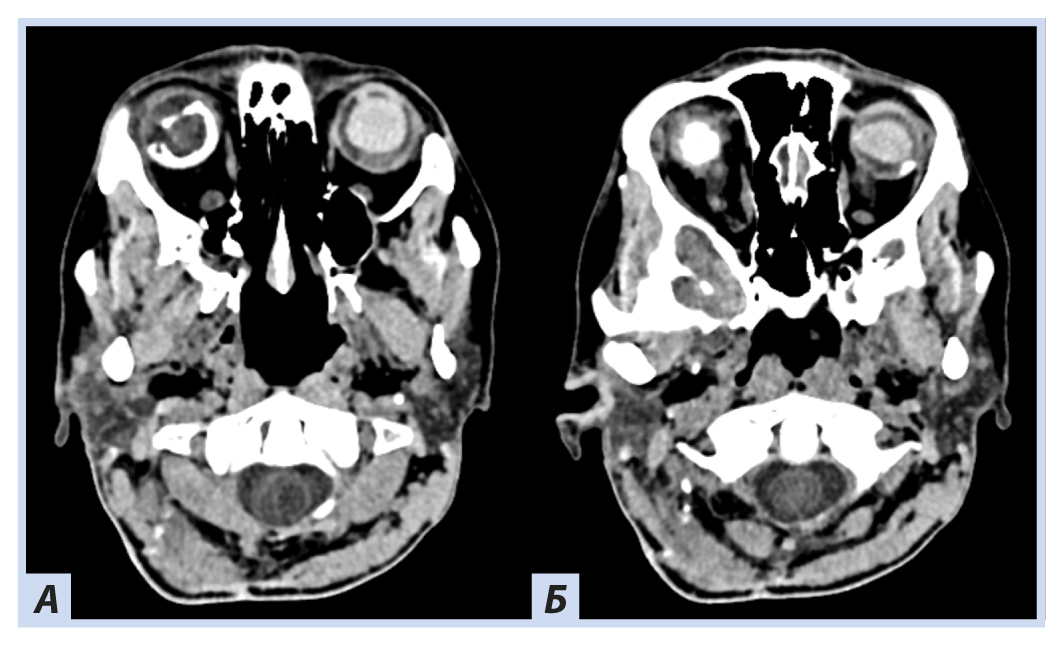

Лучевые методы. На МРТ-изображениях головного мозга выявлено характерное двустороннее поражение глаз (рис. 1), по данным КТ — с участками обызвествления (рис. 2). Также на КТ головного мозга были выявлены зона послеоперационных кистозно-глиозных изменений с наличием кисты и узла на уровне посттрепанационного дефекта в правом полушарии мозжечка, а также аналогичные зоны дорзальнее и в субкортикальных отделах; в левой гемисфере мозжечка определялись кистозные изменения (рис. 3).

Рис. 2. Пациентка П., 30 лет, с диагнозом «Болезнь Гиппеля−Линдау»: компьютерная томография головного мозга

Примечание. Отмечаются гиперденсные зоны в области сетчатки и глазных яблок справа плотностью до +270…+330 HU.